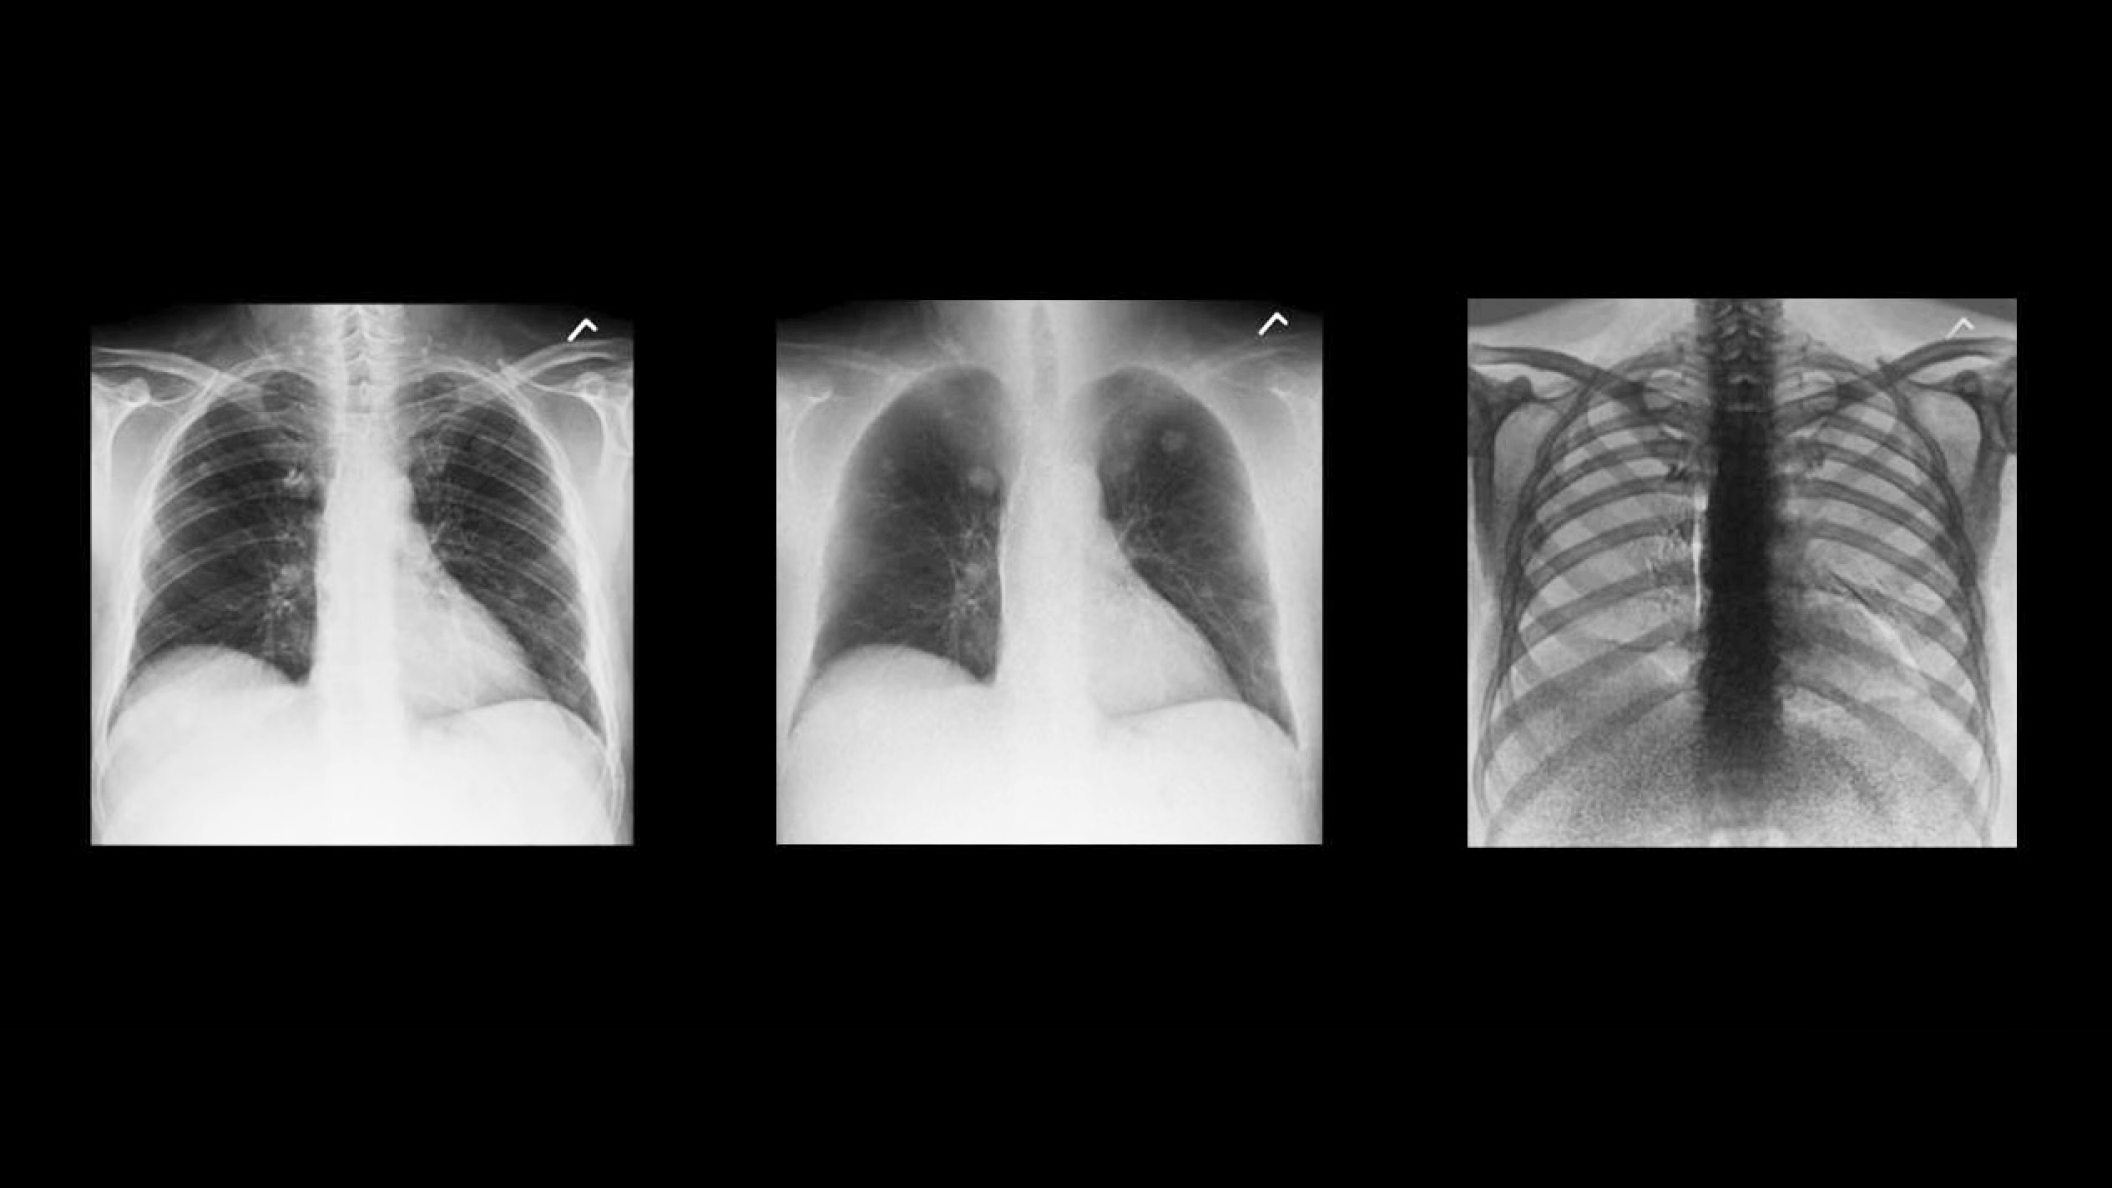

Two acquisitions. Three images.

Rather than relying solely on algorithmic image processing, Dual Energy Subtraction acquires two exposures at different energy levels in less than 160 milliseconds. You can process and view the image as:

• A standard radiographic image

• An image with bones subtracted

• An image of just the bones to highlight foreign objects or calcified structures

These images help you detect abnormalities that may have been obscured in a conventional radiograph.